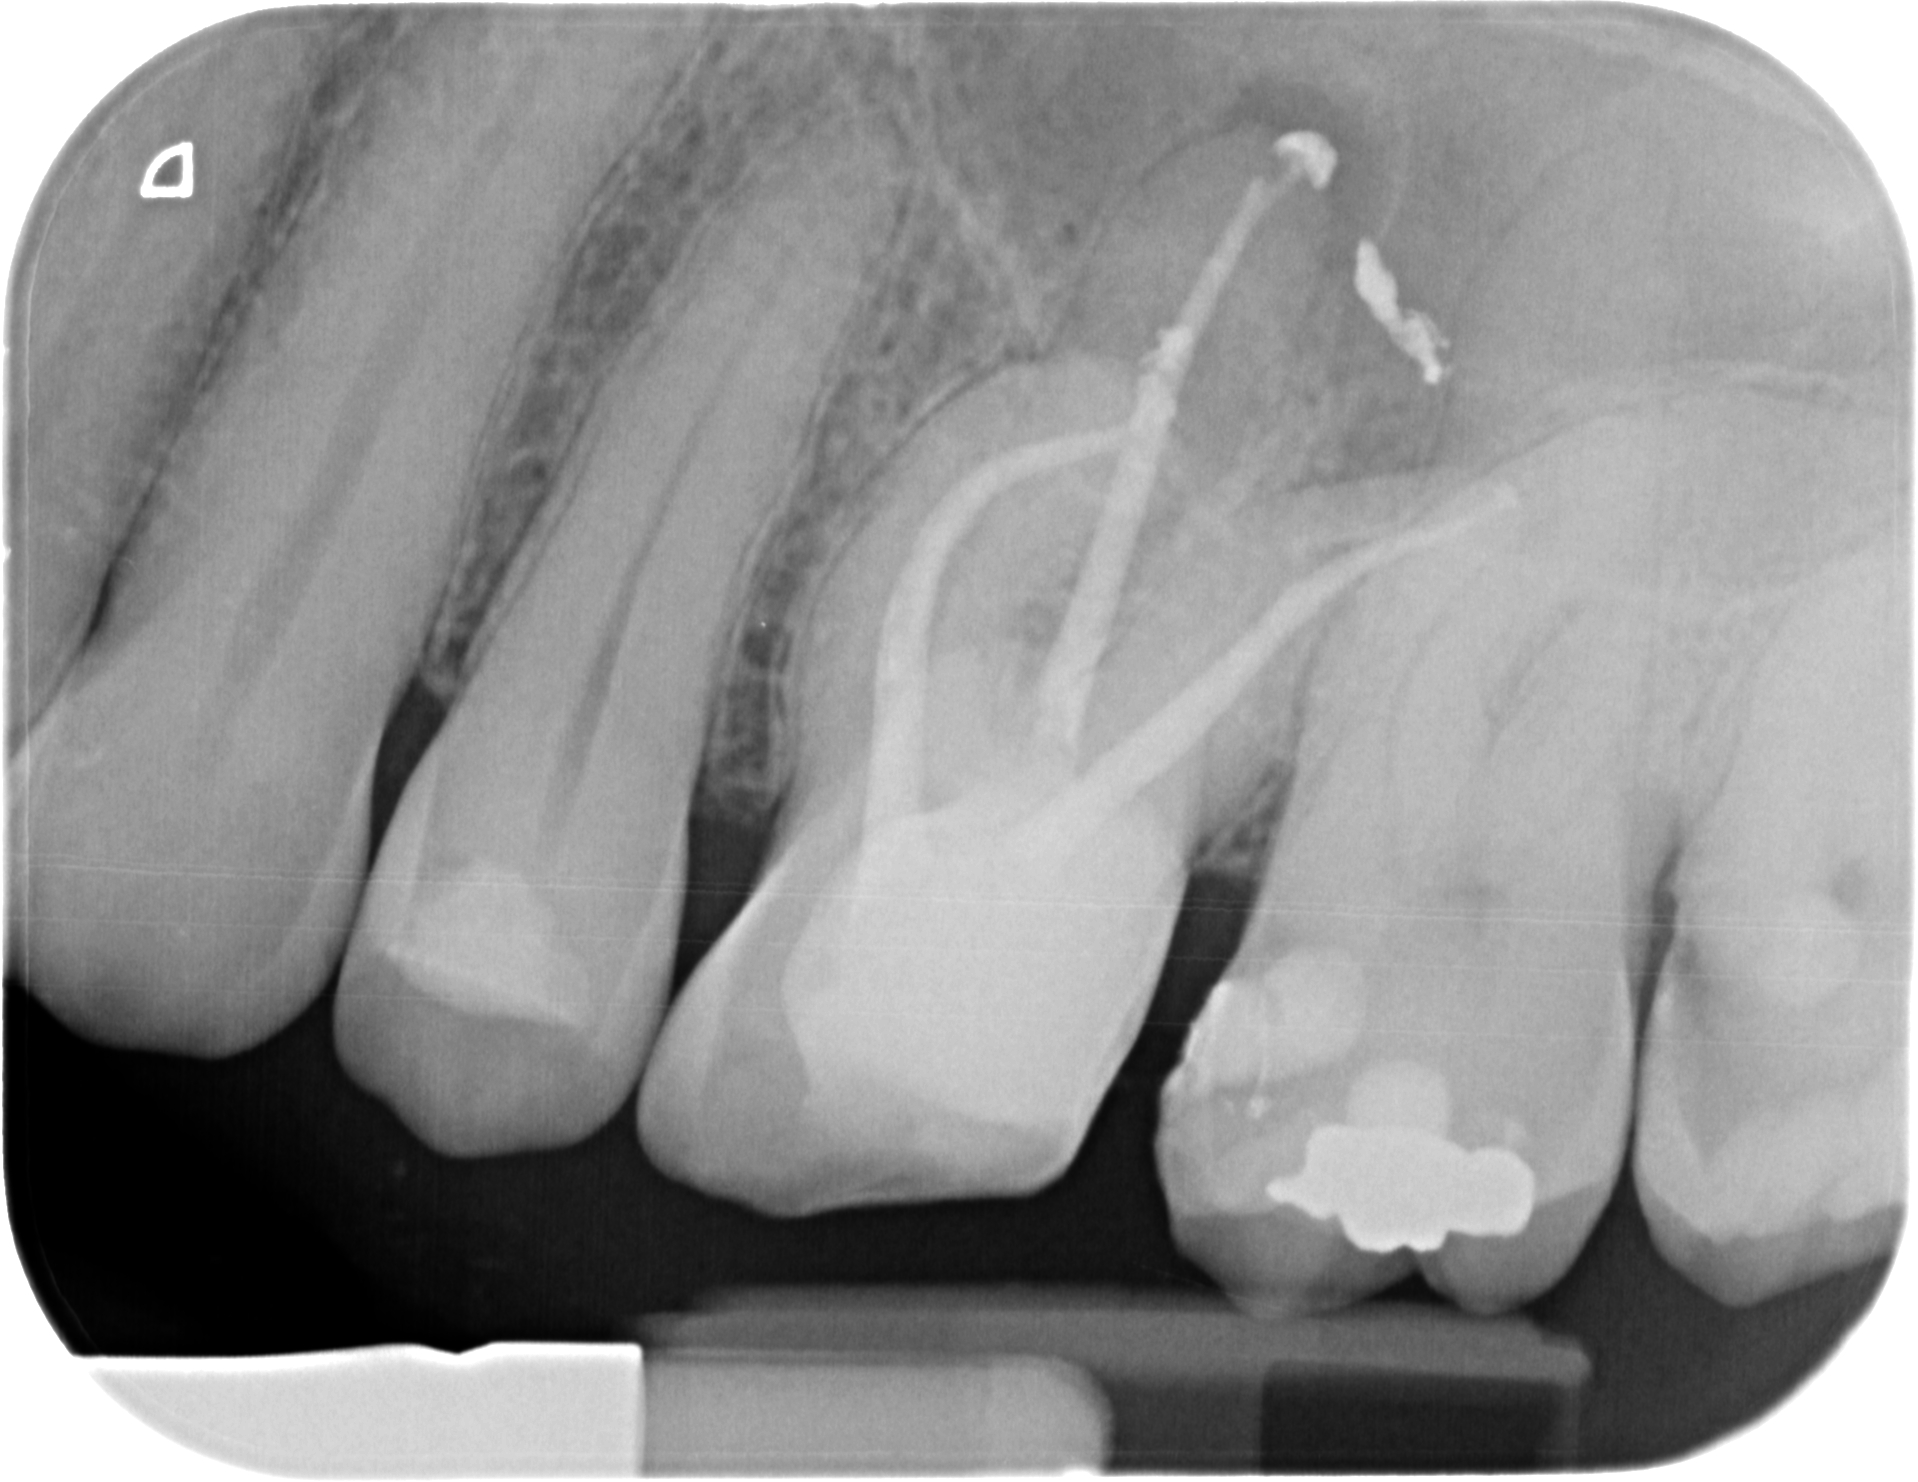

Odontología Conservadora y Endodoncia en Segovia

En Clidentse, tu clínica dental en Segovia, abordamos la odontología conservadora y la Endodoncia, especialidades dedicadas al mantenimiento de los dientes en boca, con la finalidad de devolver al diente su integridad anatómica y funcional.

La Endodoncia es la especialidad que permite conservar el diente en boca cuando la patología pulpar del diente es ya irreversible.

Durante una endodoncia, vulgarmente conocida como “matar el nervio”, lo que hacemos es eliminar el tejido pulpar (el nervio) enfermo y conformar y desinfectar todo el sistema de conductos radiculares, para luego rellenar y sellar esos conductos de un material termoplástico. A continuación hay que Reconstruir la corona mediante técnicas adhesivas, bien con composite o si la reconstrucción es muy grande, recurrimos a la Porcelana como mejor material para restituir la integridad funcional y anatómica perdida.